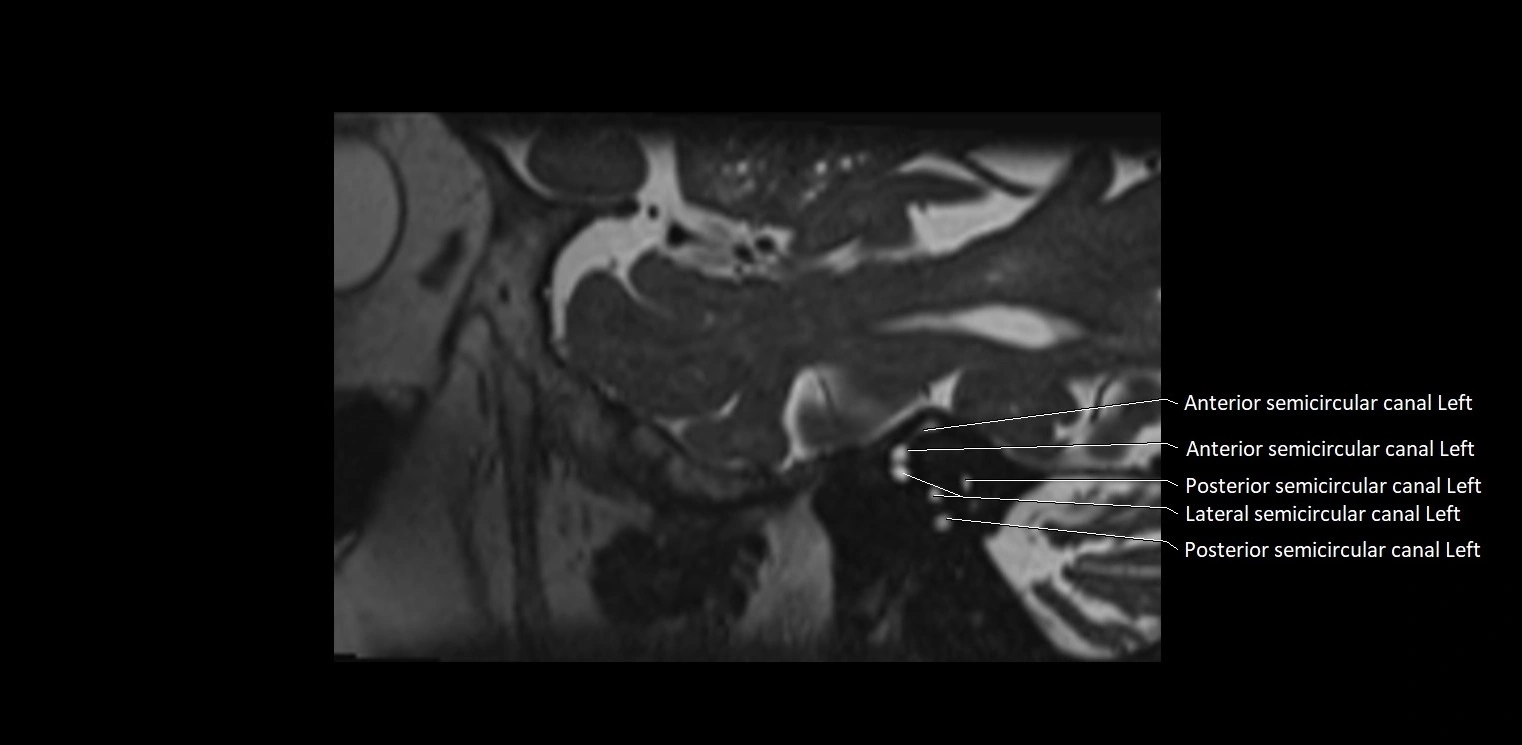

MRI images

image